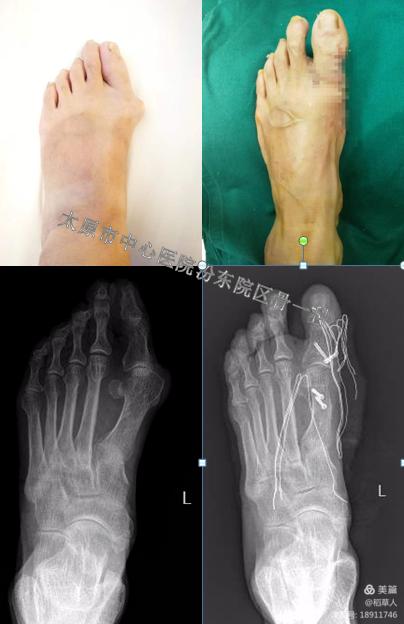

这是一位57岁的大娘,术后疼痛明显缓解,等她完全康复后,又可以愉快的去跳广场舞了。